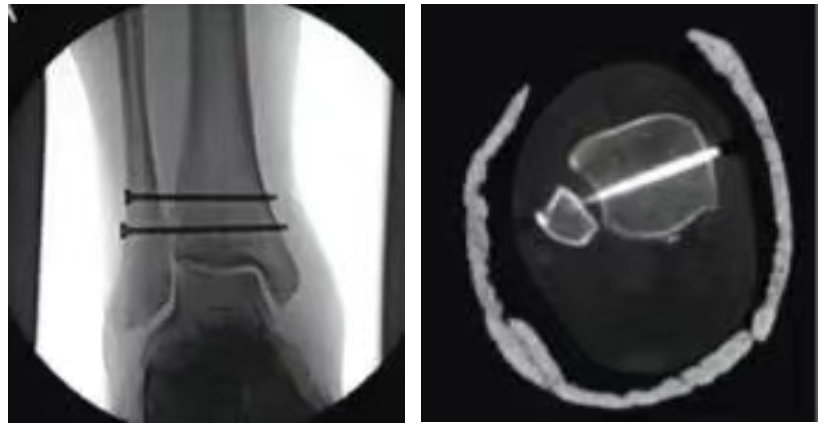

傳統(tǒng)手術(shù):剛性固定

金屬接骨螺釘固定脛骨及腓骨,恢復(fù)下脛腓關(guān)節(jié)穩(wěn)定性

脛腓前韌帶可逐漸瘢痕愈合

十二周后取出接骨螺釘